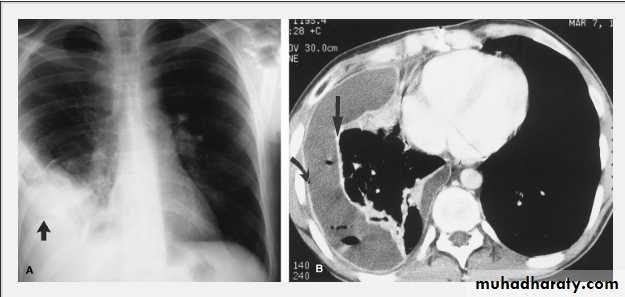

Tension pneumothorax.

On a posteroanterior chest x-ray (A), the left hemithorax is very dark or lucent because the left lung has collapsed completely (white arrows).

The tension pneumothorax can be identified because the mediastinal contents, including the heart, are shifted toward the right, and the left hemidiaphragm is flattened and depressed. A computed tomography scan done on a different patient with a tension pneumothorax (B) shows a completely collapsed right lung (arrows) and shift of the mediastinal contents to the left.

chest practice

Tension Pneumothorax. Portable chest film in a 43-year-old woman with ARDS shows a large right pneumothorax with mediastinal shift and ipsilateral diaphragmatic depression, suggesting tension.

Air was evacuated under pressure during emergent placement of a right chest tube.